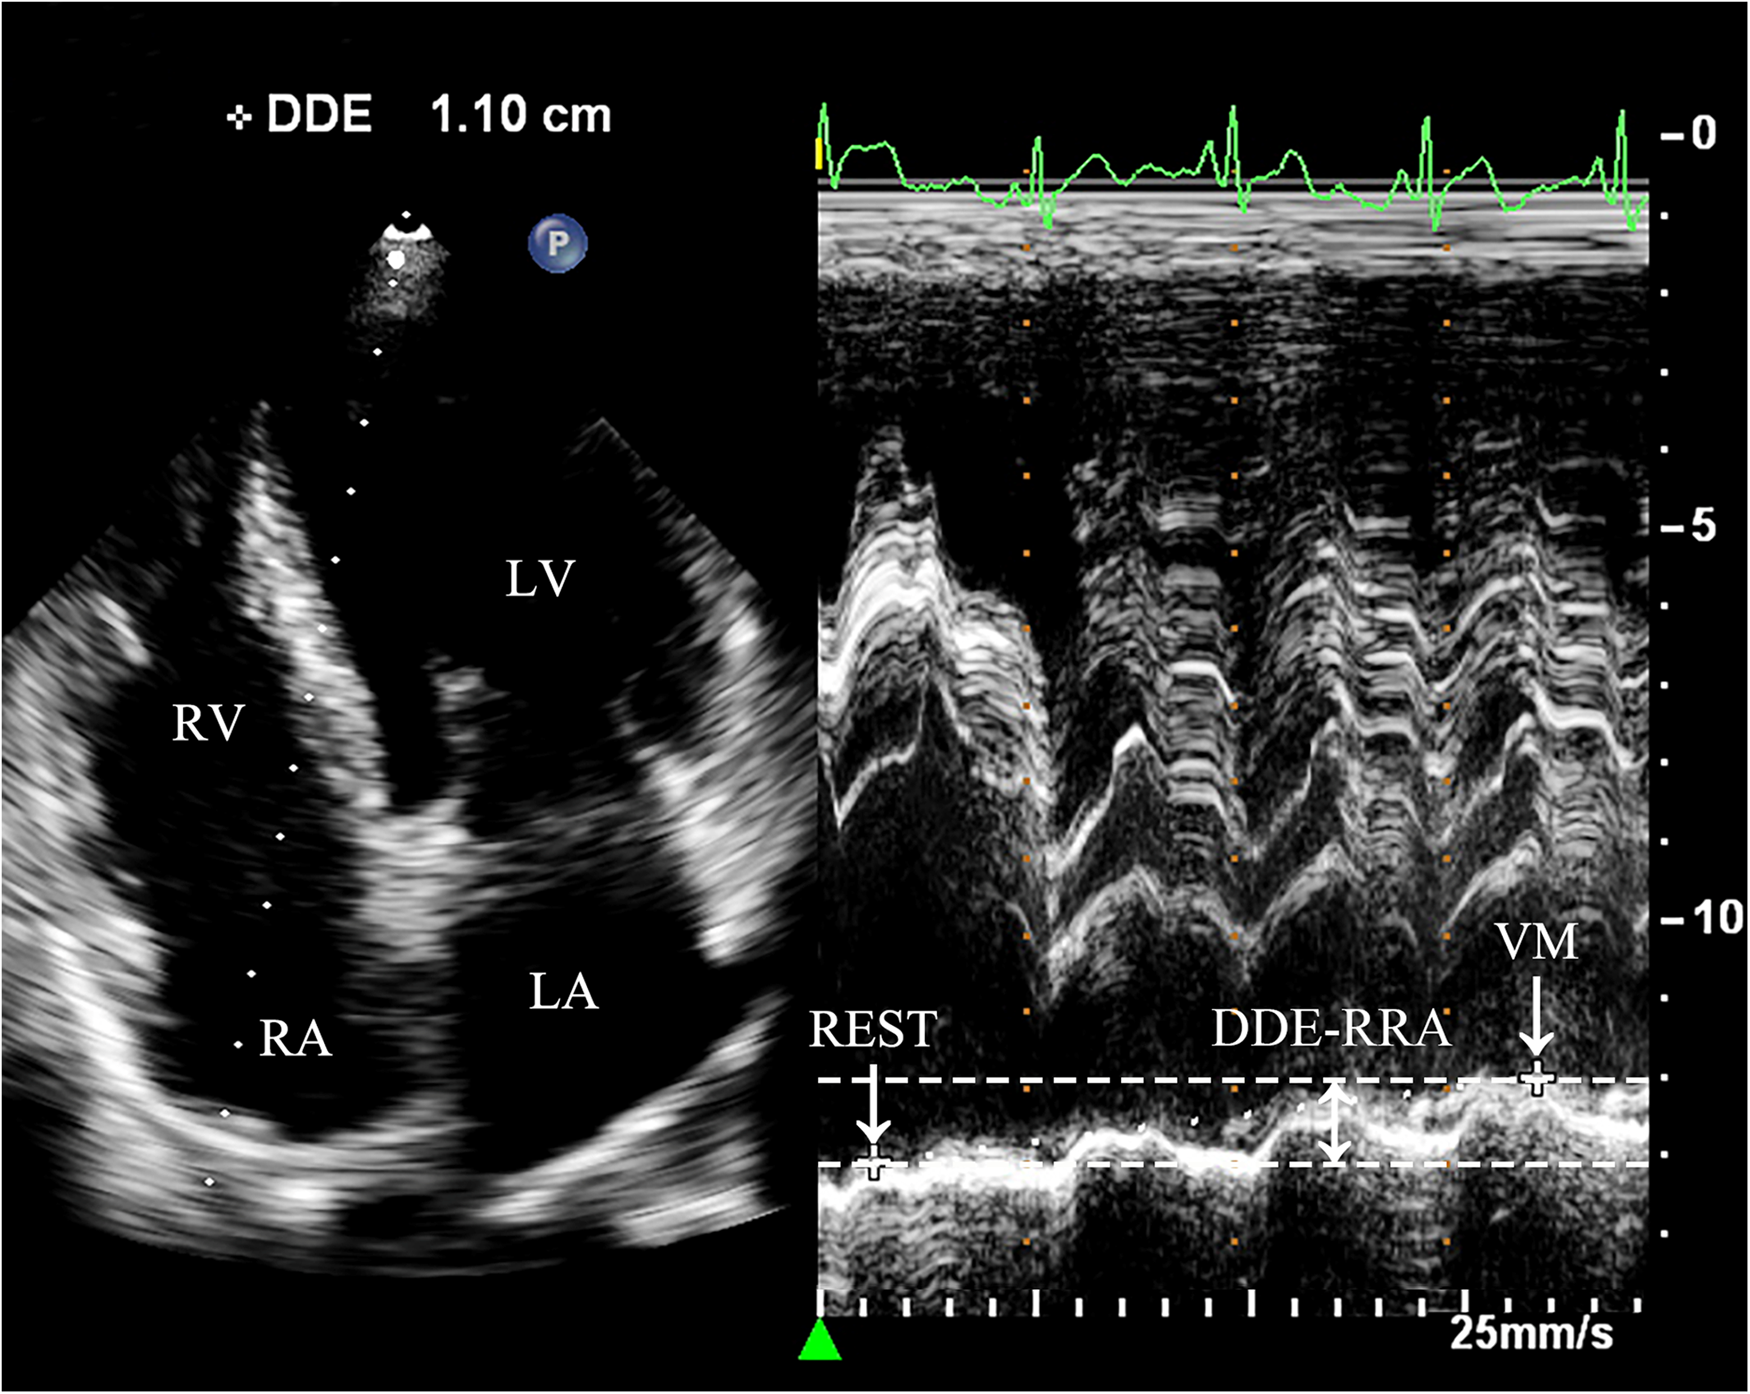

Diaphragmatic downward excursion at the roof of the right atrium (DDE-RRA): In apical four-chamber view, a sampling line for M-mode ultrasonography is positioned at the roof of the right atrium. The patient was then instructed to perform VM to measure the maximum vertical distance of the diaphragmatic downward excursion while holding their breath. This measurement is referred to as DDE-RRA (Figure 2).

Figure 2

Measurement of DDE-RRA. Dramatic diaphragmatic downward excursion is observed. In the apical four-chamber view, the sampling line is placed across the top of the right atrium to obtain the M-mode motion curve of the diaphragm. REST refers to the moment right before the subject initiates the Valsalva maneuver, when they are in a baseline or resting state. VM refers to the point when the subject is holding their breath for 10 s during the Valsalva maneuver, just before releasing the breath. DDE-RRA (double-headed arrow) is the measured value representing the difference in the diaphragm's position between two distinct time points. REST, at rest; VM, Valsalva maneuver; LA, left atrium; LV, left ventricle; RA, right atrium; RV, right ventricle; DDE-RRA, diaphragmatic downward excursion at the roof of the right atrium.